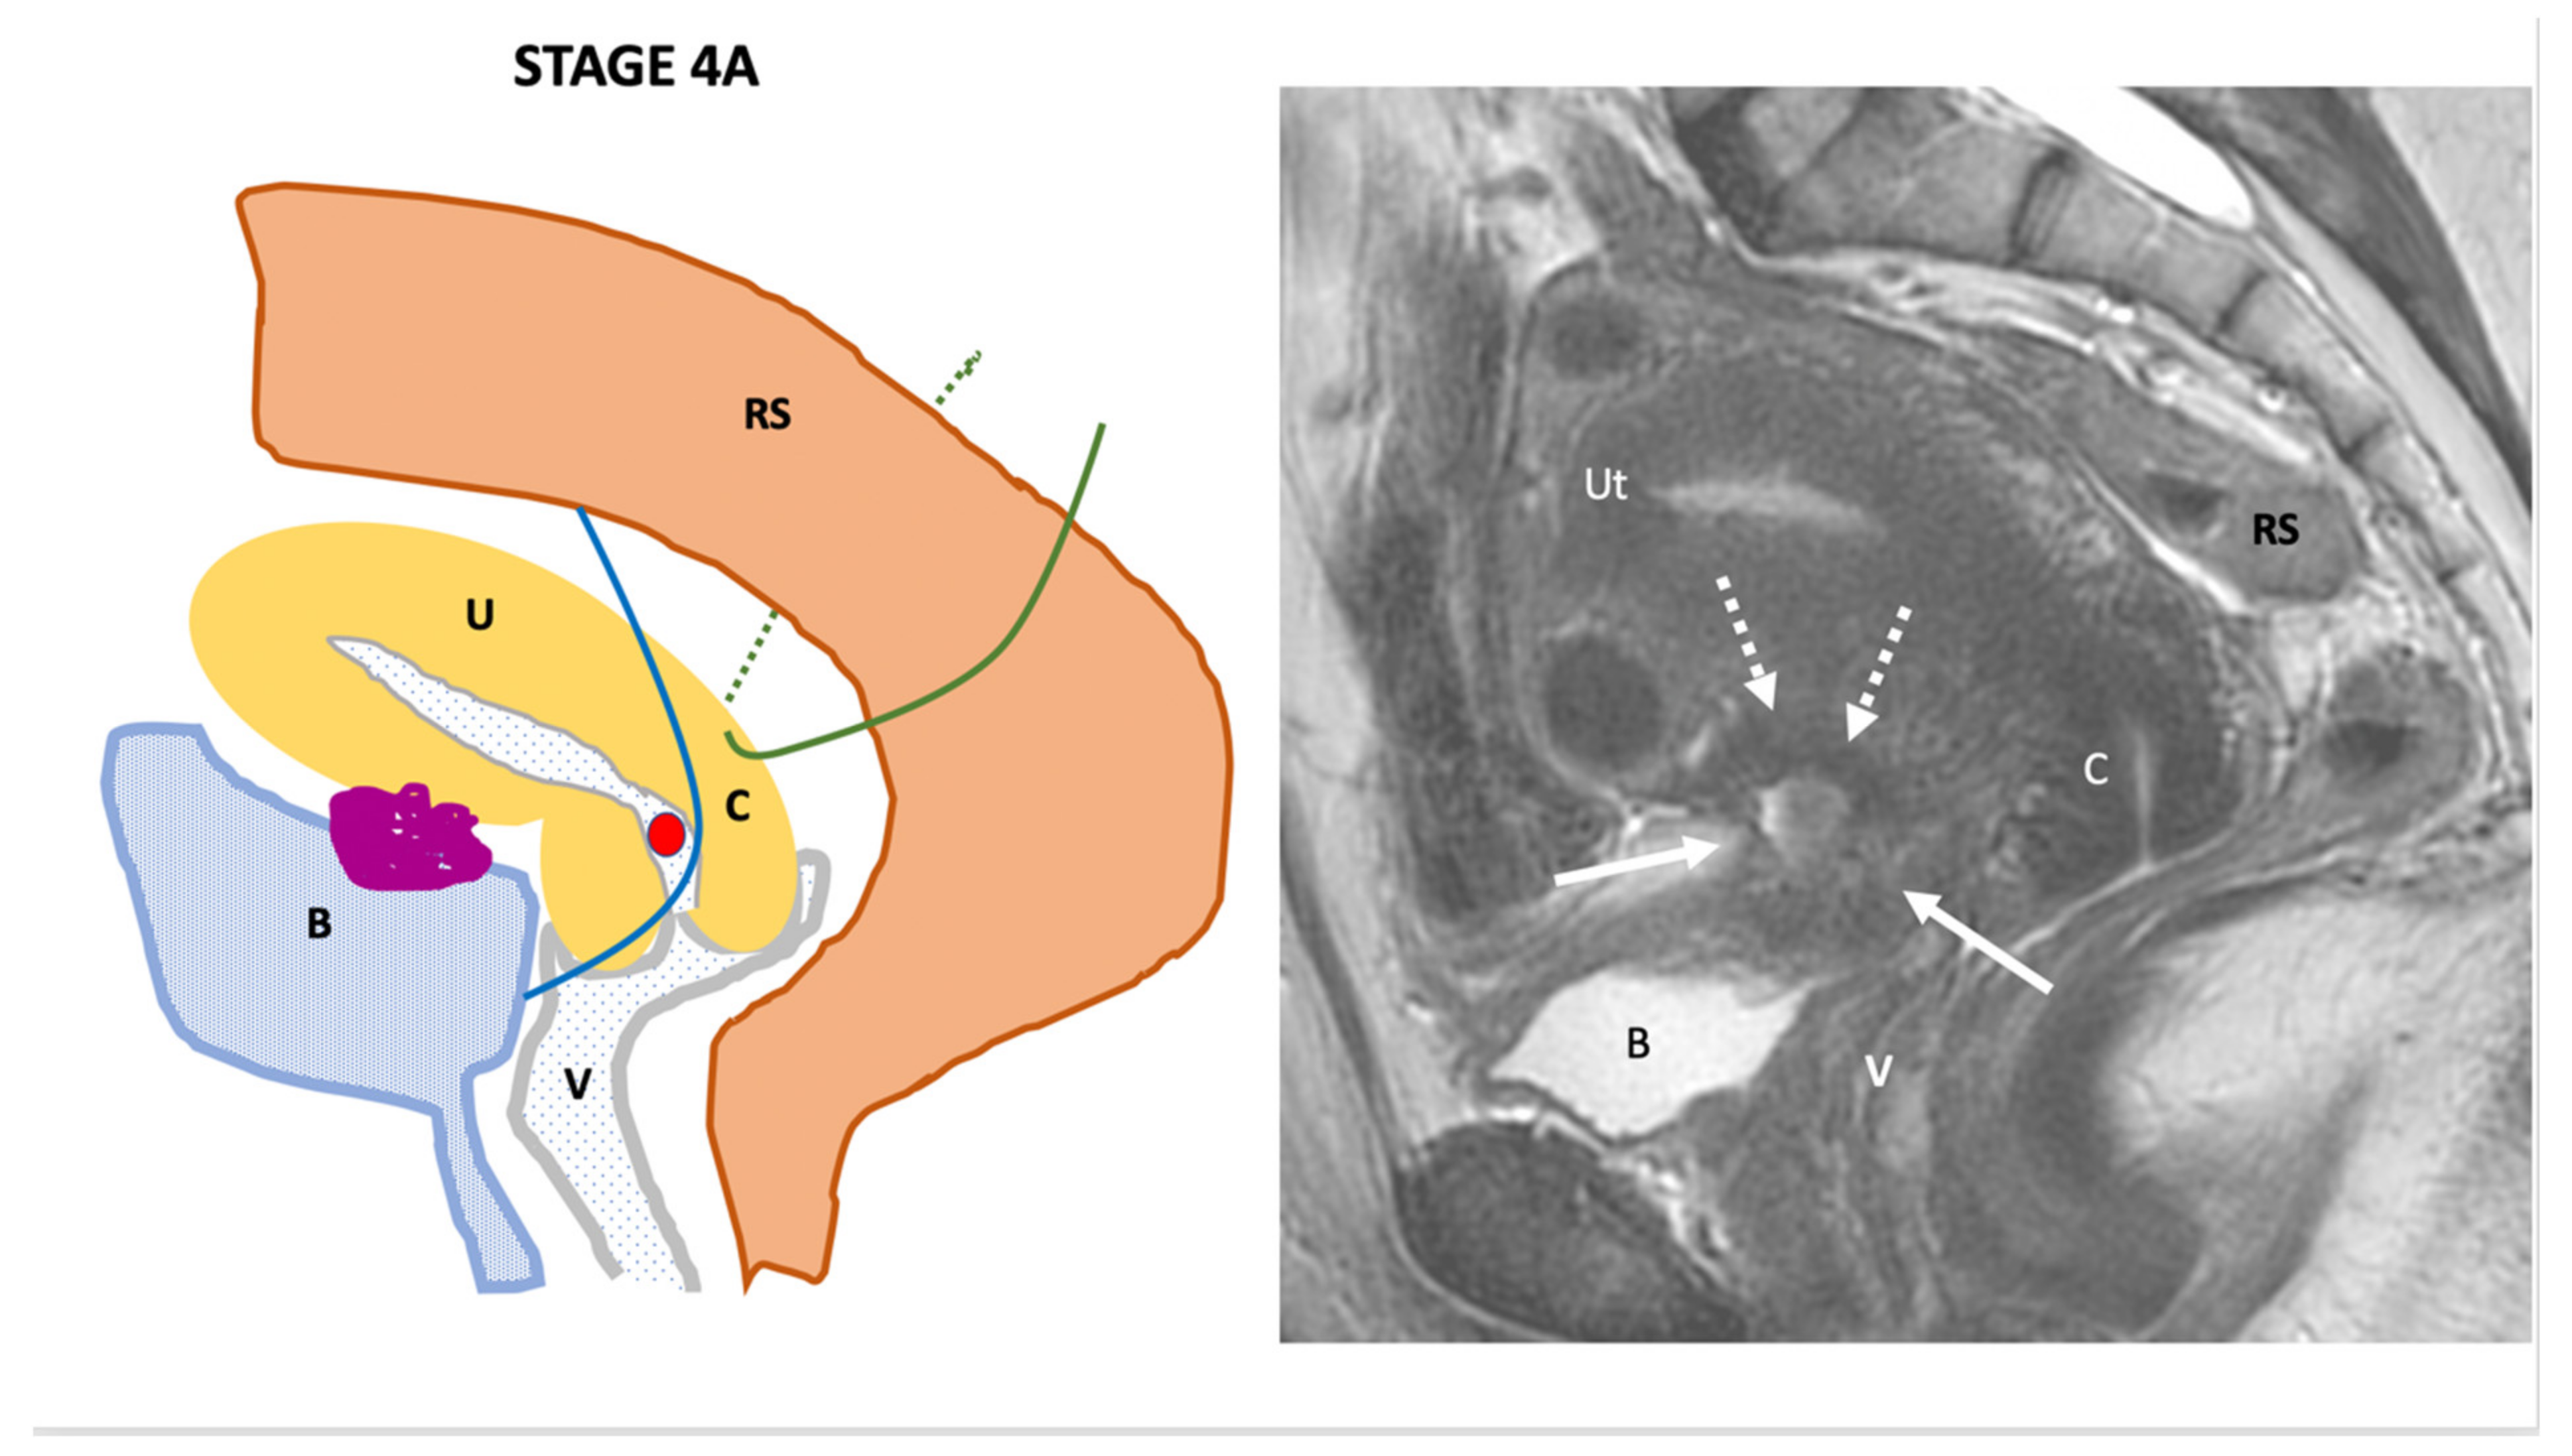

| Endo-Stage MRI 0 | Superficial endometriosis |

| Low |

| Endometriosis is strictly confined to the ovaries |

| ||

| Endo-Stage MRI I | Endometriosis is strictly confined to the retrocervical area |

| |

| Endo-Stage MRI II | Endometriosis invades beyond the retrocervical area, but not to the pelvic side-wall |

| Endo-Stage MRI III | Endometriosis extends to the pelvic side-wall and/or causes hydronephrosis or non-functioning kidney |

| Intermediate |

| Endo-Stage MRI IV | Endometriosis has involved the bladder or rectosigmoid colon |

| Endo-Stage MRI V | Multiple deep endometrioticlocations |

| High |